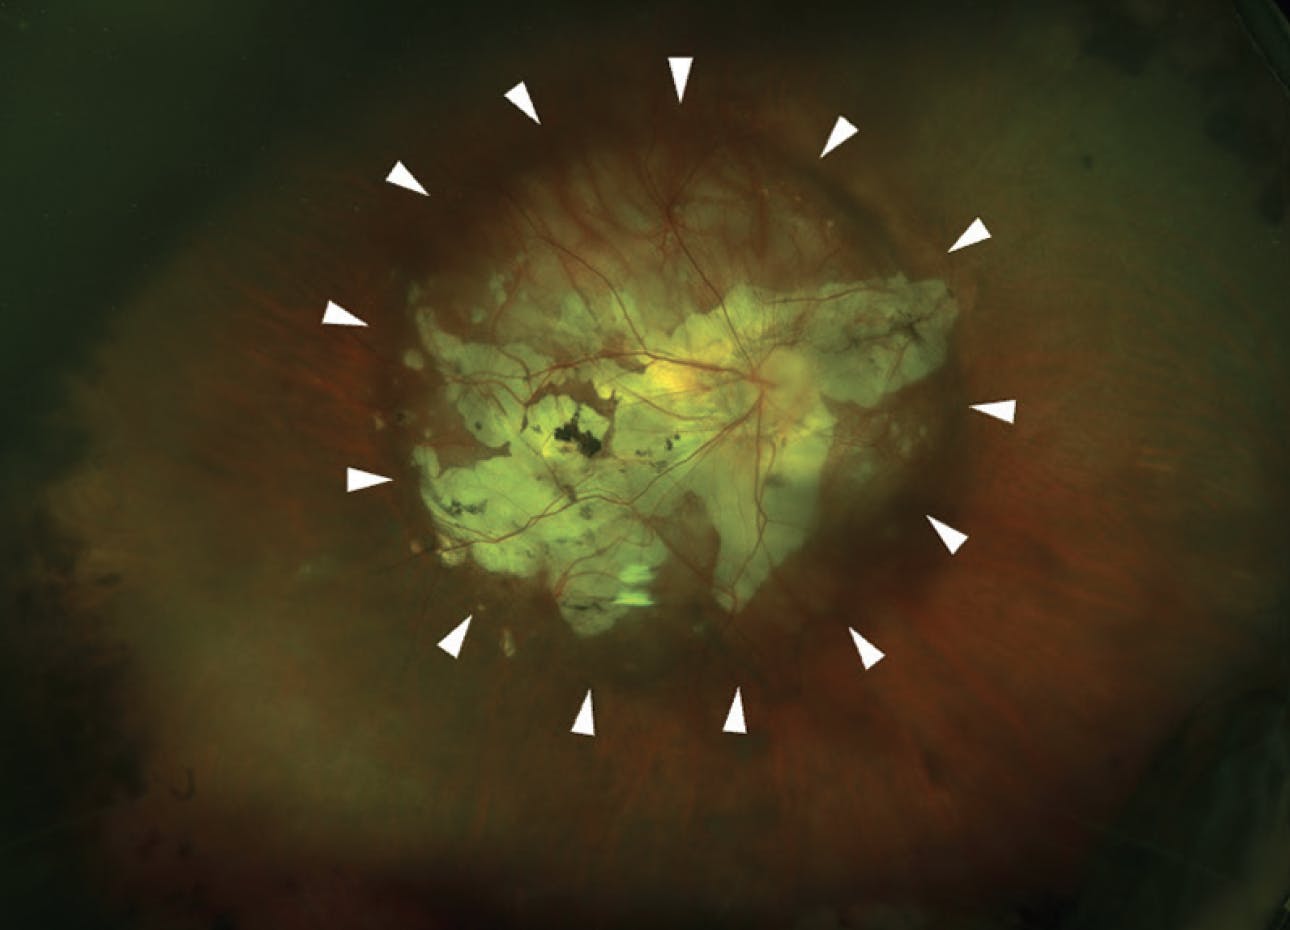

Beyond the detection of macular lesions in eyes with pathologic myopia, clinicians must remember the large spectrum of peripheral lesions in highly myopic eyes. Ultra-widefield color fundus photography and ultra-widefield OCT have been widely used in recent years for the detailed assessment of posterior staphylomas, a hallmark of pathologic myopia. While the initial 1977 classification of posterior staphylomas identified 10 different types of posterior staphyloma on fundus examination,12 there was no universally accepted definition. More recently, Ohno-Matsui et al used ultra-widefield color fundus photography and 3D MRI to visualize the entire extent of posterior staphylomas and critical features of staphyloma edges, such as gradual choroidal thinning from both sides, scleral inward protrusion, and posterior scleral displacement (Figures 5 and 6).13

<p>Figure 5. Ultra-widefield color fundus photography shows a wide macular staphyloma with pigmentary changes at the staphyloma edges (arrows) and large areas of patchy atrophy.</p>

Figure 5. Ultra-widefield color fundus photography shows a wide macular staphyloma with pigmentary changes at the staphyloma edges (arrows) and large areas of patchy atrophy.